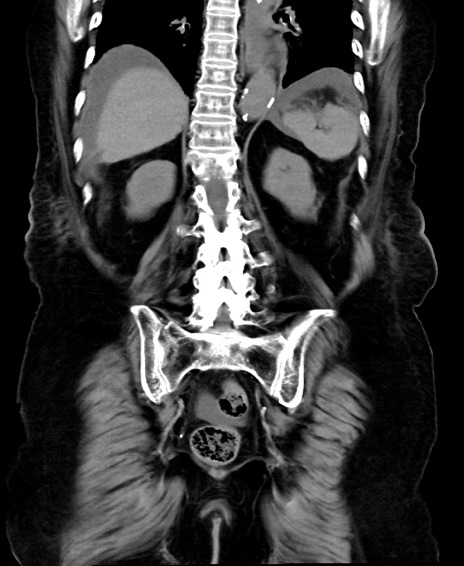

冠状断像